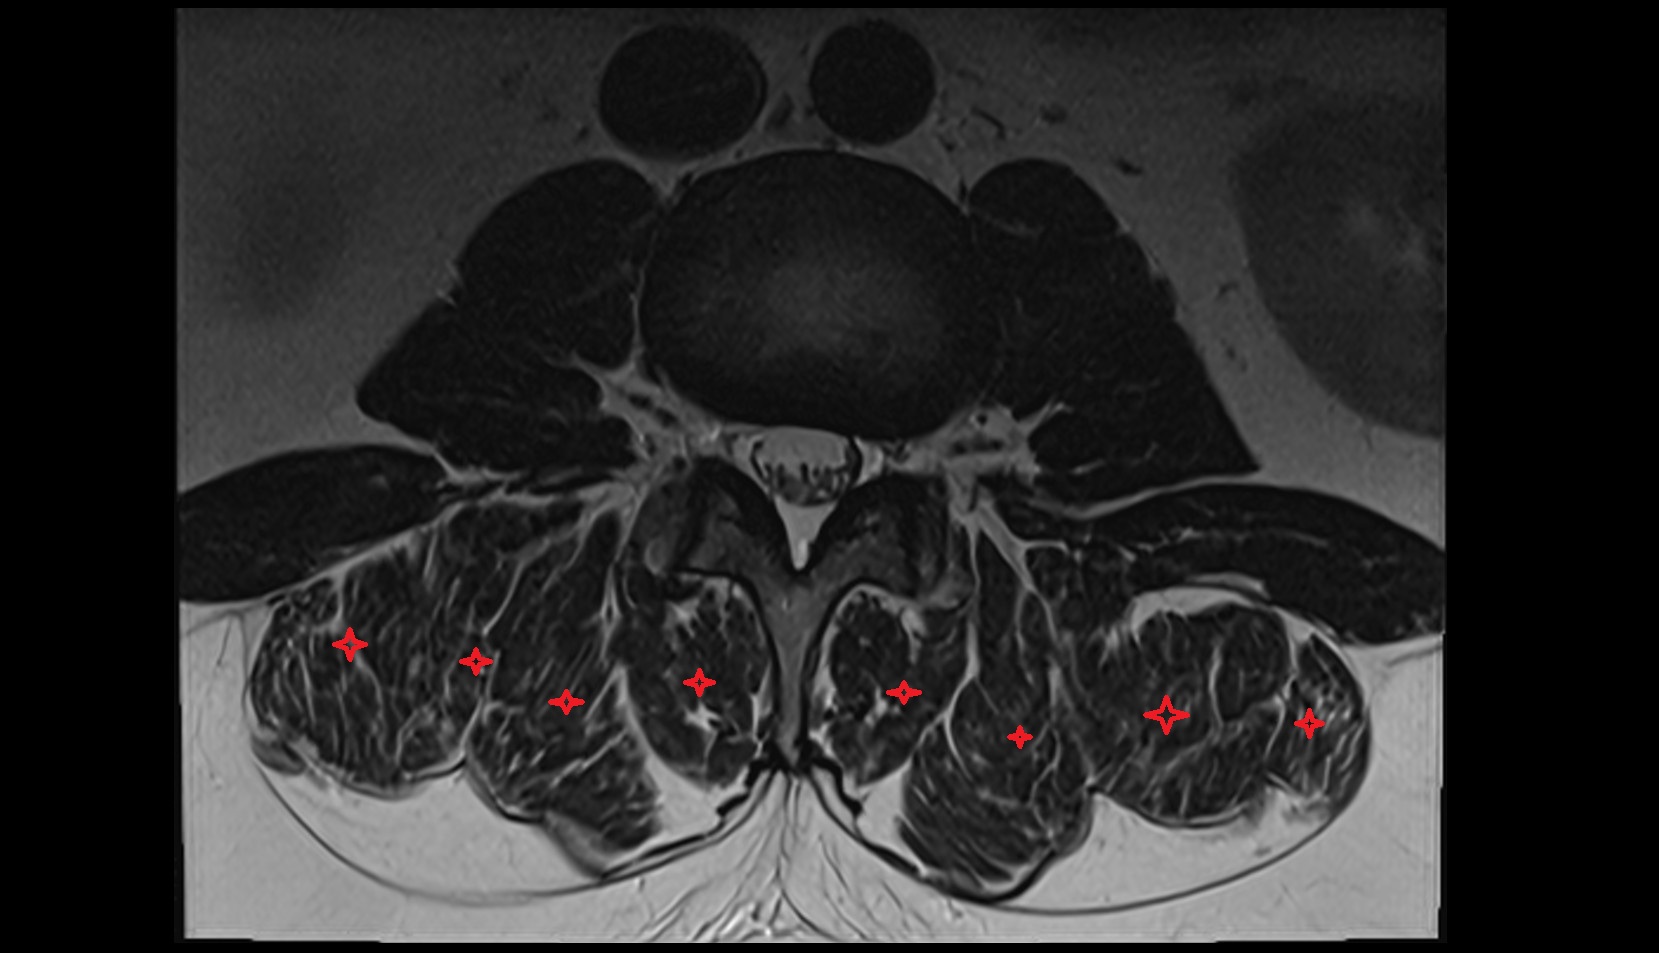

- Cauda equina

- Conus medullaris